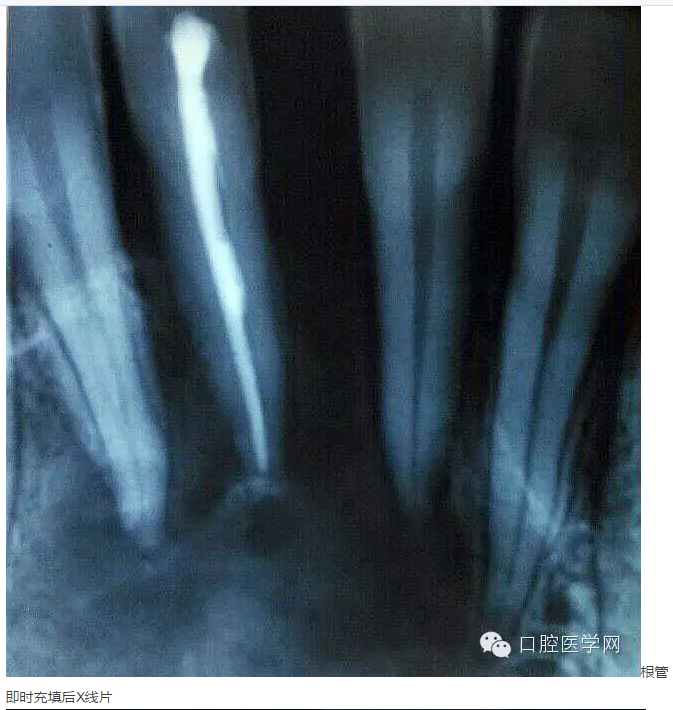

下面是一例 今年年初治療的下前牙根尖囊腫病例,患者因故未能按時(shí)復(fù)診,最近才來(lái)。